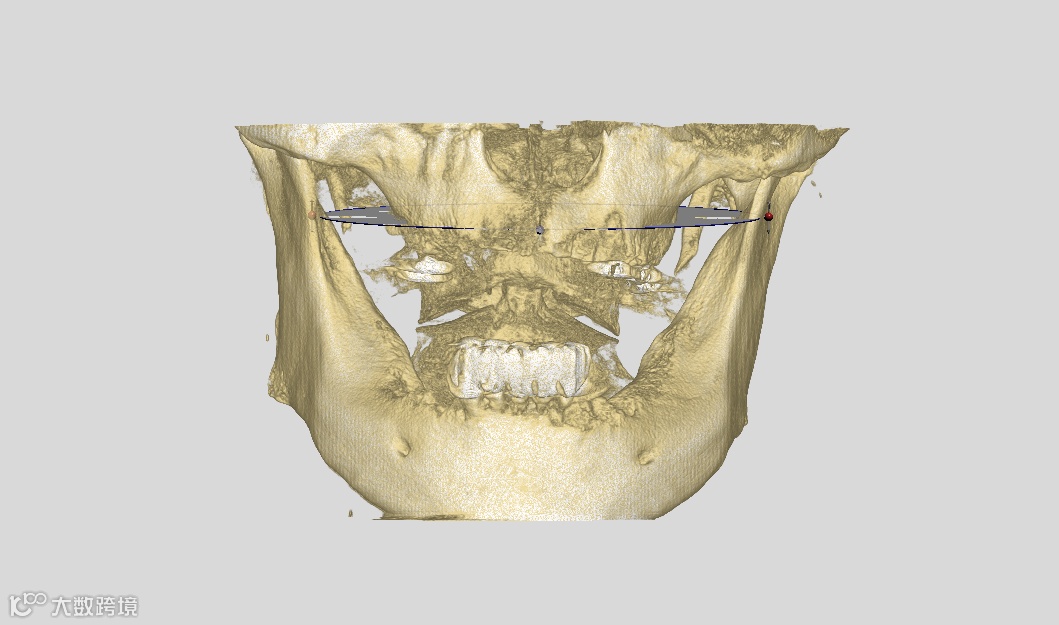

数字化种植手术规划与导板设计